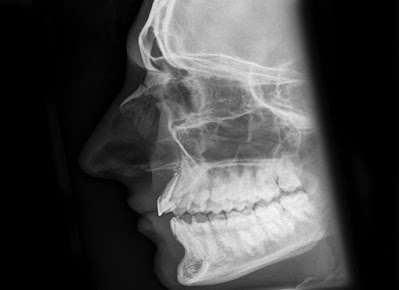

![]() |

| آشعة عادية توضح كسر الأنف |

- آشعة عادية (إكس راي) على عظام الأنف، منظر جانبي: مهم جداً من الناحية القانوينة أيضاً.